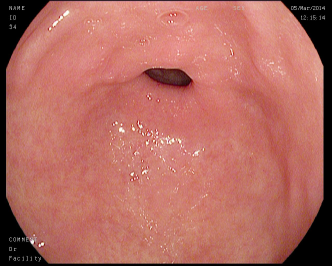

4.1.7 Gastrointestinal endoscopy

Endoscopies are used to detect diseases in the human digestive system. Images from inside the gastrointestinal tract can be used to help doctors detect diseases early. The used dataset 777https://www.kaggle.com/datasets/abdallahwagih/kvasir-dataset-for-classification-and-segmentation contains eight image categories of the digestive system obtained through the endoscopy imaging technique, as shown in Fig. 8. There are a total of 6000600060006000 images that can be used in training and testing machine learning algorithms.

Refer to caption

(a) Normal cecum

(b) Normal pylorus

(c) Normal z-line

(d) Dyed lifted polyps

(e) Dyed resection margins

(f) Esophagitis

(g) Polyps

(h) Ulcerative-colitis

Figure 8: Gastrointestinal endoscopy images.